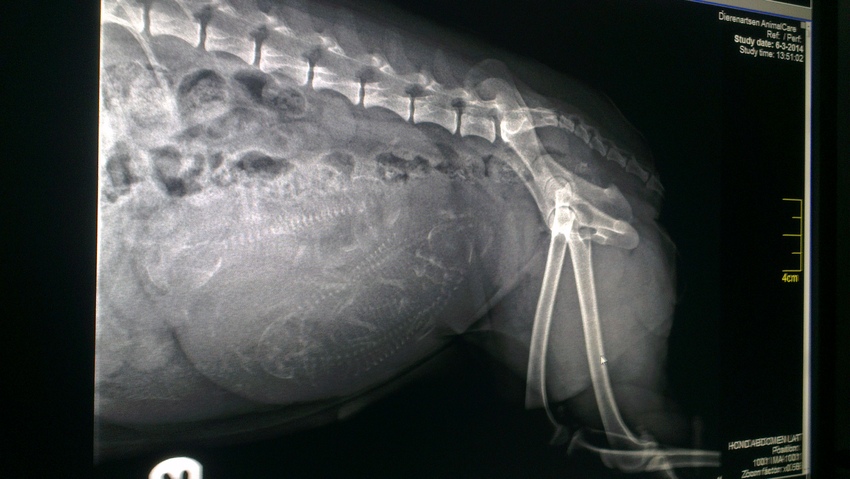

Merle had vannacht een onrustige nacht.. veel hijgen,soms een harde buik en erg veel kreunen en zuchten. Overdag heeft ze het niet meer gehad al hijgt ze nog regelmatig. Maar omdat ik het niet helemaal vertrouwde toch even laten controleren door een dierenarts. Alles voelde goed en haar temperatuur is normaal. Toch hebben we om onszelf even gerust te stellen en foto laten maken, en daar was duidelijk te zien dat haar darmen erg vol zijn. Waarschijnlijk had ze wat voorweeën vannacht (wat niet abnormaal hoeft te zijn) en had ze er zoveel last van omdat de pups op haar volle darmen drukte. Nu dus vaker naar buiten en haar meer rust geven en dus geen lange wandelingen meer. Maar het leuke nieuws, ze draagt 4 pups! En de kans is er dat er een 5e is. De foto's zijn na elkaar gemaakt maar de pups liggen erg verschillend en door haar volle darmen kan je op die plek niet veel zien. Dus nu maar hopen dat ze het nog minstens een week uit houd, al hoop ik nog wat langer!